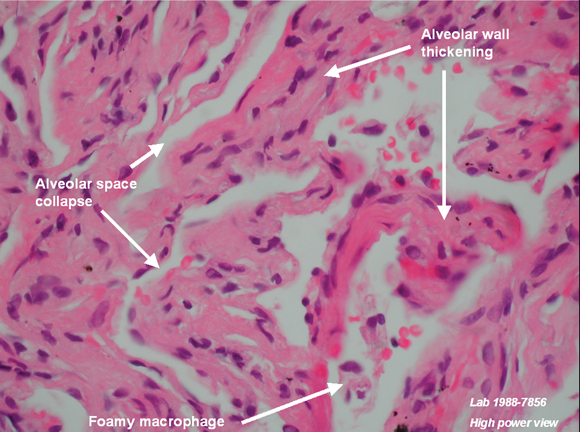

HRCT: bilateral ground glass infiltrates, fibrosis, some traction bronchiectasis TLCO: 44%, mildly obstructed flow volume loop Lavage: 38% eosinophils, 15% lymphocytes, 5% neutrophils Biopsy: thickened alveolar walls with interstitial fibrosis, minimal inflammation ANA-negative

One previous case of pneumonitis has been reported in the setting of statin therapy, which was confirmed by open lung biopsy, and where the findings closely resembled those in amphiphilic drug toxicity, such as that reported with amiodarone. The authors hypothesised that a toxic mechanism, possibly mediated by statin effects on lipid metabolism, led to the observed intralysosomal lamellar inclusions in pneumocytes and interstitial cells.9 Thus, while not fully characterised, there is a putative mechanism through which statins may cause interstitial pneumonitis.